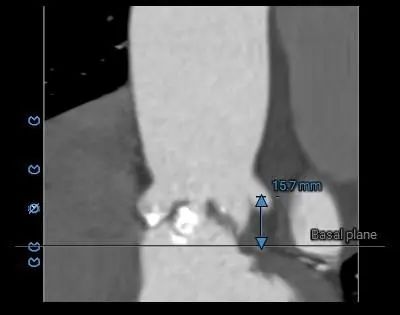

主动脉瓣环水平夹角71度,严重横位心,主动脉弓宽度、角度尚可,弓部存在散在钙化

虚拟瓣环与水平夹角